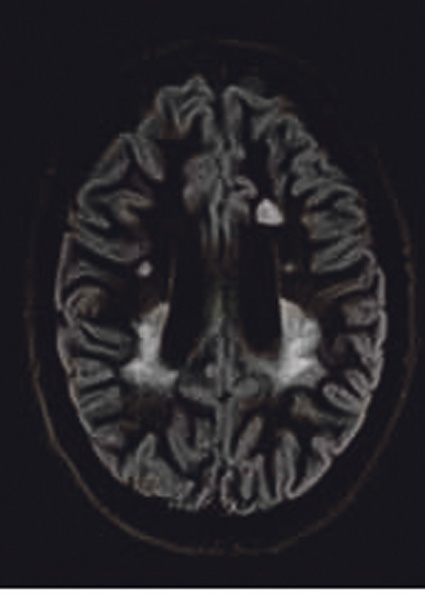

Die Leistungsfähigkeit des Vantage Titan 3T wird derzeit bei Toshibas Kooperation mit Prof. Frederik Barkhof, Chef der Neuroradiologie der VUMC (Vrije Universiteit Amsterdam Medical Center), unter Beweis gestellt. In dieser Kooperation werden z. B. neueste Sequenzen zur Untersuchung von MS- und Alzheimer-Patienten entwickelt und optimiert. Ein Ergebnis dieser Forschungsaktivitäten ist eine verbesserte 3D-Double-Inversion-Recovery-Sequenz (3D-DIR) zur verbesserten Visualisierung von MS-Plaques, die schon in Kürze in der neuesten Software-Version für alle interessierten Nutzer zur Verfügung stehen wird. Eine weitere Sequenz aus dem Bereich der suszeptibilitätsgewichteten Sequenzen (SWI) wird zurzeit genauer evaluiert. Denn neben Toshibas sehr empfindlicher FSBB (Flow Sensitive Black Blood)-Sequenz sind die Forscher auch an einer weniger empfindlichen FIBB (Flow Insensitive Black Blood)-Sequenz interessiert, da sie Pathologien mit Eisenanreicherungen weniger stark betont wiedergibt.

Dies ist sicherlich eine Forschungskooperation, in der es sinnvoll ist, auch die 32-Kanal-Kopfspule einzusetzen und beim Optimieren das letzte Quäntchen Signal auszuschöpfen, wie es auch bei der funktionellen Bildgebung genutzt wird. Eine in der Routine viel häufigere Anwendung wird dagegen eine neue T2-FSE-Sequenz für die Wirbelsäulenbildgebung haben, die unempfindlicher auf Flussartefakte ist und wie die neue mEcho für die transversale T2*-Bildgebung schnell im nächsten Software-Release zur Verfügung steht. Zusammen mit der 3D-DIR-Sequenz sind es dann drei Neurosequenzen, die schnell ihren Weg von der Entwicklung in die Routine finden.